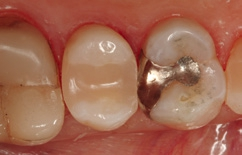

Die Weiterversorgung erfolgte nach adhäsiver Vorbehandlung mit einem approximal eingebrachten 4-mm-Inkrement SDR flow+ (Dentsply Sirona) in der Farbe A3, klassisch überschichtet mit ceram.x universal in der Farbe A3,5. Die Wahl auf ein Bulk-Flow-Komposit approximal fiel aufgrund der optimalen selbstnivellierenden Adhäsion zum Adhäsiv und somit zur Reduktion potenzieller Fehlerquellen in der Schichttechnik, die Wahl zugunsten des eingefärbten SDR flow+ in der Farbe A3 entgegen der transluzenten Universalfarbe U aufgrund der im Approximalraum dunkel erscheinenden Gold-Restauration am Nachbarzahn. Dies ergab in der Vergangenheit bei Verwendung von SDR flow+ U oft ein unschönes „grau-transluzent“ erscheinendes Bild der Kompositrestauration im Approximalraum. Ästhetisch störte dies meist nur bedingt, suggerierte aber immer die latente Möglichkeit einer Approximalkaries. Durch die Verwendung der Farbe A3 bei SDR flow+ war ein derartiges grau-transluzentes Erscheinungsbild nicht mehr gegeben; die Restauration erscheint homogener (Abb. 5). Die Abbildung 6 zeigt die Röntgenkontrollaufnahme nach einem Jahr, die Abbildung 7 die klinische Situation: Der Zahn ist weiterhin vital, symptomlos und beschwerdefrei. Direkte Kompositrestaurationen stellen heute gerade bei vorangegangenen Goldinlay-Kavitäten die suffizienteste Sekundärversorgung dar: Der vorhandene Federrand kann belassen werden und muss nicht in eine plane Stufe einer Keramikrestauration umpräpariert werden.

Im Röntgenbild ist kein Unterschied in der Röntgenopazität zwischen SDR flow+ und ceram.x universal auszumachen, obwohl 2/3 der approximalen Kavitätentiefe von SDR flow+ ausgefüllt wird. Da hinsichtlich ihres Indikationsspektrums direkte Kompositrestaurationen eine ideale Alternative zu Inlayversorgungen darstellen und zudem substanzschonender sowie kosteneffizienter sind, bleibt heute kaum mehr eine wahre Indikation für Inlayversorgungen. Klinisch bewährt hat sich die direkte Kompositversorgung gerade bei dem Austausch kleinerer Goldinlays [13,14].